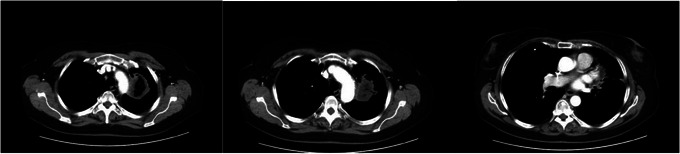

成人费城染色体阴性急性淋巴细胞白血病复发的发生率估计为40%-50%。异基因干细胞移植可提高复发性急性淋巴细胞白血病患者的生存率然而,肺功能受损对移植过程的存活是不利的。在此,我们报告一例成功的异基因移植治疗因血管浸润性肺毛霉菌病而完全切除左肺后复发的b急性淋巴细胞白血病。据我们所知,这是首例全肺切除术后同种异体移植成功的病例。该病例的具体考虑包括仔细的供体选择,明智地选择移植前调节方案,并利用新的免疫疗法确保移植前主要残留疾病阴性。我们希望这个病例能为临床医生提供额外的指导,帮助他们治疗恶性血液病患者,这些患者发展为侵袭性真菌感染,需要进行大的肺部手术。

The incidence of relapsed Philadelphia chromosome-negative acute lymphoblastic leukemia in adults is estimated to be 40%-50%. Allogeneic stem cell transplantation can improve survival in relapsed acute lymphoblastic leukemia; however, impaired pulmonary function is detrimental for surviving the transplantation process. Here, we present a successful case of allogeneic transplantation for relapsed B-acute lymphoblastic leukemia after total resection of the left lung due to angioinvasive pulmonary mucormycosis. To our knowledge, this is the first successful case of allogeneic transplantation after total pneumonectomy. Specific considerations in this case included careful donor selection, judicious choice of pre-transplantation conditioning regimen, and utilizing novel immunotherapies to ensure major residual disease negativity prior to transplant. It is our hope that this case provides additional guidance to clinicians caring for patients with hematologic malignancies who develop invasive fungal infections and require major lung surgeries.